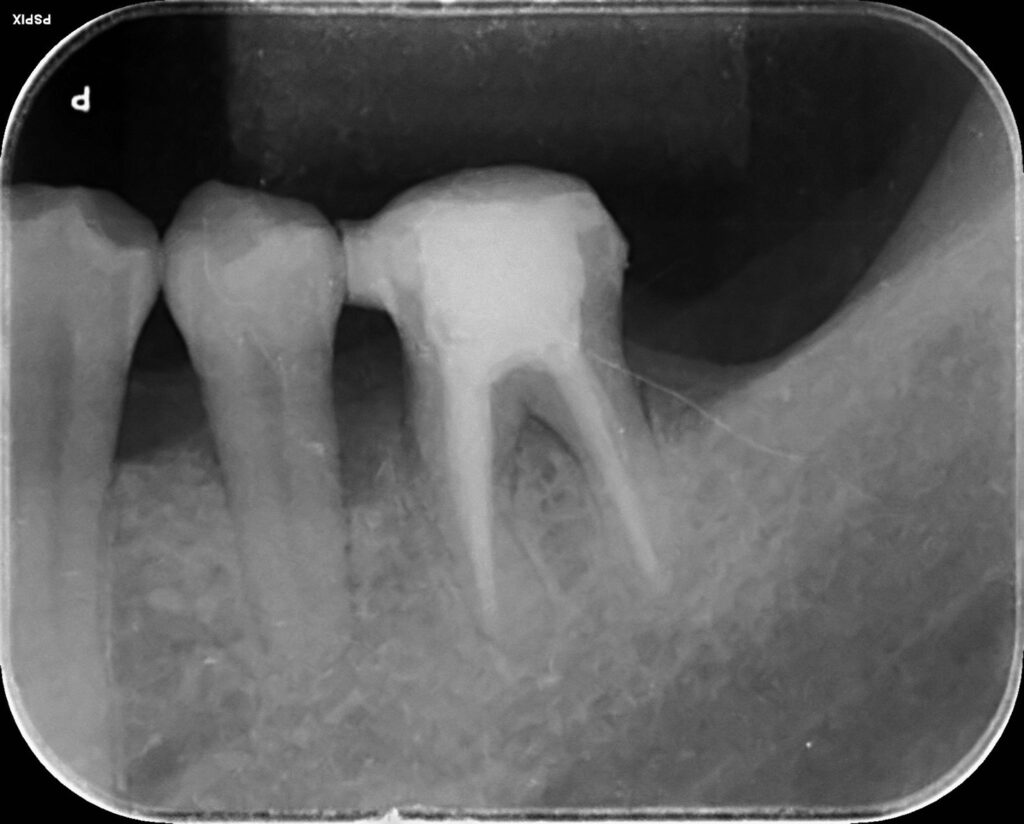

治療前

治療後